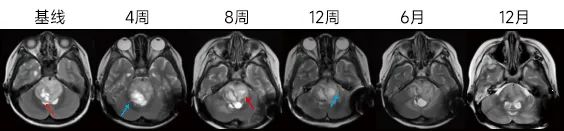

研究组根据患者影像特征来决定 Ommaya 囊的数量和植入顺序。图 2 患者行基线筛查时,影像提示病灶在脑干的右侧,初步的治疗方案定为右侧病灶的活检和 Ommaya 囊置入。患者在接受计划的治疗后于外院行放射治疗。然而,在放射治疗结束后,患者再次返院行随访,头颅 MRI 提示脑干左侧新发占位。为排除放射治疗导致的坏死或者假性进展,再次对该病灶进行了活检,术中病理结果回报为高级别胶质瘤。考虑到右侧化疗囊不能很好地覆盖左侧脑干占位,因此进行了第二次左侧 Ommaya 囊的植入手术,从双侧进行病毒的注射增加病毒扩散的面积。在 6 个月和 12 个月的随访中,脑干双侧的肿瘤体积均显著缩小。

肿瘤体积均显著缩小。

图 2:某患者的治疗流程以及影像学变化